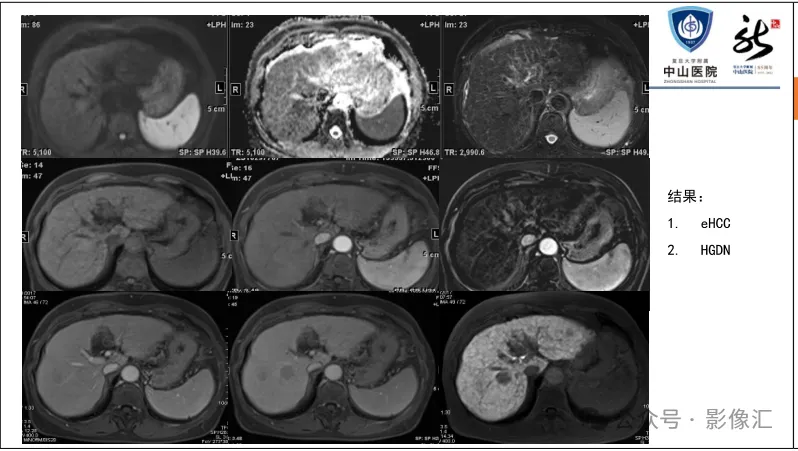

肝胆特异性对比剂增强肝胆图像判读方法与策略,课件来源于网络,作者复旦大学附属中山医院放射科饶圣祥教授。